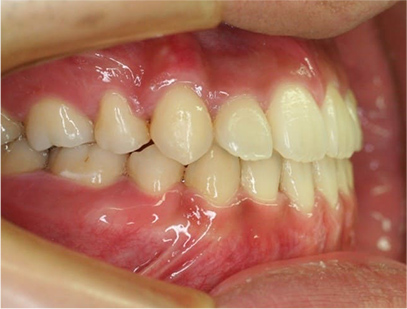

前歯にデコボコがあり、前歯が咬み合っていない症例

上下の前歯が咬んでいない事、上の前歯にデコボコがある事を主訴として来院されました。

通常通りの検査を行い「前歯部にデコボコを伴う開咬」と診断されました。

治療前

• 右側

• 左側

治療前の写真を比べると上下の前歯は綺麗に並び、歯が出ていたことも改善され、 上下の歯はしっかり咬み合っています。 治療期間は、重度の開咬であったために3年弱を必要としました。